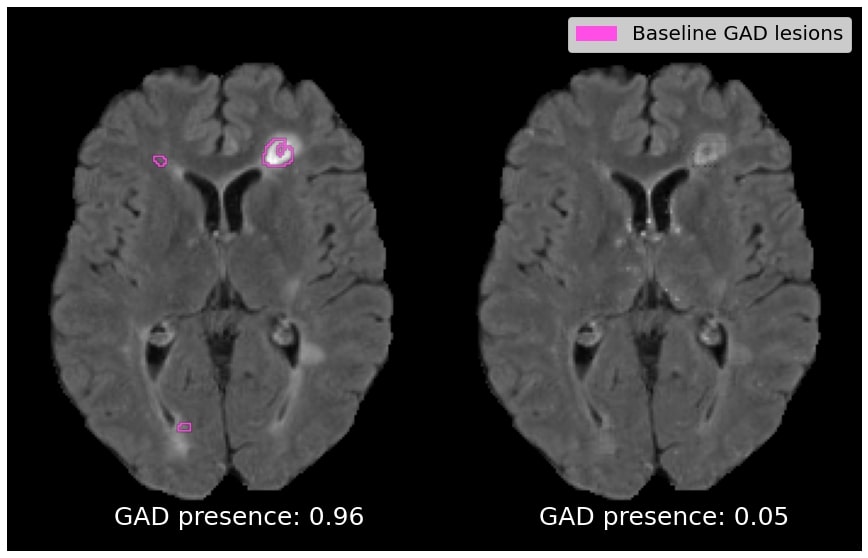

Target Class Similarity Quantitative results depicting the average T2 lesion volumes and Gad lesion prevalence for the reconstruction and generated counterfactual image are reported in Table 2. For comparison, we also include T2 lesion volume and Gad lesion prevalence statistics for real active and real inactive samples. In the top row, we see that the average T2 lesion volume of the reconstruction is relatively close to that of the real active samples. On the other hand, the average T2 lesion volume of the counterfactual is substantially lower, being closer to the T2 lesion volume of the real inactive subjects than the active subjects. A similar trend can be observed for Gad lesion prevalence, where the Gad prevalence of the generated counterfactual has dropped closer to the prevalence observed among real inactive subjects. Overall, these results show that the counterfactual images are realistic in terms of their ability to discover clinically established population-level predictive markers, without a priori knowledge of these markers. In this case, this leads to a reduction in baseline T2 lesions load and a removal of baseline Gad lesions from the counterfactual images.

Figure 4 depicts qualitative results for the effect on T2 and Gad lesion load. In (a), we show an example of a patient with above-average lesion load, with the counterfactual exhibiting a 79% drop in T2 lesion load. In (b), an active patient is shown with a below-average lesion load (i.e. an example that goes against the population-level trend), with the counterfactual exhibiting a 54% drop in T2 lesion load. In (c) and (d), the counterfactual images exhibit a complete suppression of Gad lesions. Overall, Gad lesions are suppressed to a much greater extent than T2 lesion suppression. This aligns with the statistics for real active and real inactive populations (see Table 2).